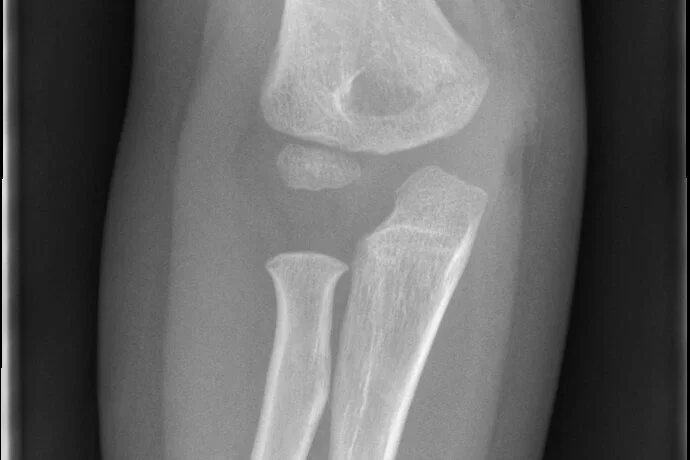

AI Project - Automated Identification and management guidance of pediatric elbow fractures